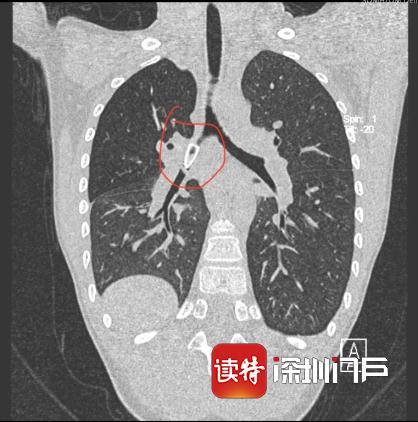

CT结果显示 , 笔帽卡在小成右侧主支气管腔内 , 诊断为右侧主支气管腔内异物 , 导致他的右肺通气不足 , 需手术取出 。